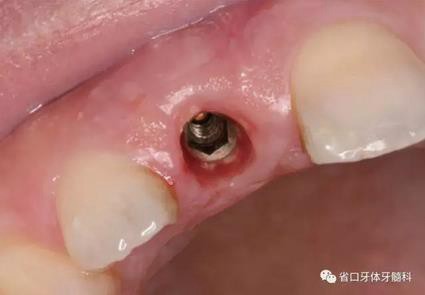

圖1 術(shù)前口內(nèi)照

圖2 術(shù)前口內(nèi)照

圖3 術(shù)前口內(nèi)照

(1)微創(chuàng)拔牙及即刻種植:術(shù)前拍攝口內(nèi)照及實(shí)施牙周基礎(chǔ)治療。常 規(guī)消毒鋪巾阿替卡因局麻下微創(chuàng)拔除上頜右側(cè)中切牙,搔刮拔牙窩及根尖肉 芽組織。探測牙槽骨唇側(cè)骨壁及鄰面牙槽嵴完整,牙齦無撕裂。不翻瓣下于上頜右側(cè)中切牙缺隙近遠(yuǎn)中中點(diǎn)的腭側(cè)牙槽骨及根方定位,按照逐級預(yù)備的原則,緊貼牙槽窩腭側(cè)骨壁制備種植窩洞,植入Zimer®3.7mm×13mm TSV種植體1顆,植入扭矩>35N·cm,以O(shè)sstell測量種植體的ISQ值為68。 種植體平臺(tái)位于唇側(cè)齦緣中點(diǎn)下3mm,與唇側(cè)骨壁內(nèi)側(cè)面形成的跳躍間 隙約2mm,置入Bio-Oss®細(xì)顆粒骨粉0.25g,上愈合基臺(tái)關(guān)閉創(chuàng)口。術(shù)后 CBCT檢查顯示:種植體利用牙槽窩根方骨質(zhì)固位,緊貼牙槽窩腭側(cè)骨壁, 其唇側(cè)面與牙槽窩唇側(cè)骨壁的內(nèi)側(cè)面所形成的跳躍間隙(約2mm)可見顆 粒狀顯影物充填。牙槽窩的唇側(cè)骨壁及唇側(cè)倒凹無缺損穿孔。